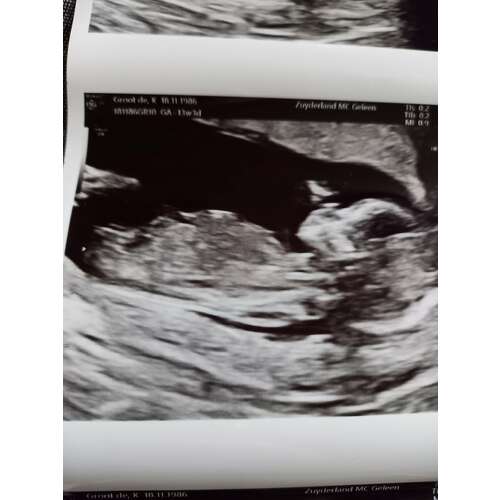

Hi Nubster, dit was 12 weken. Ben benieuwd 🙊

Waarschijnlijk 💙 had je nog een andere foto?

Allleen deze nog, is een screenshot uit een video die ik heb mogen ontvangen